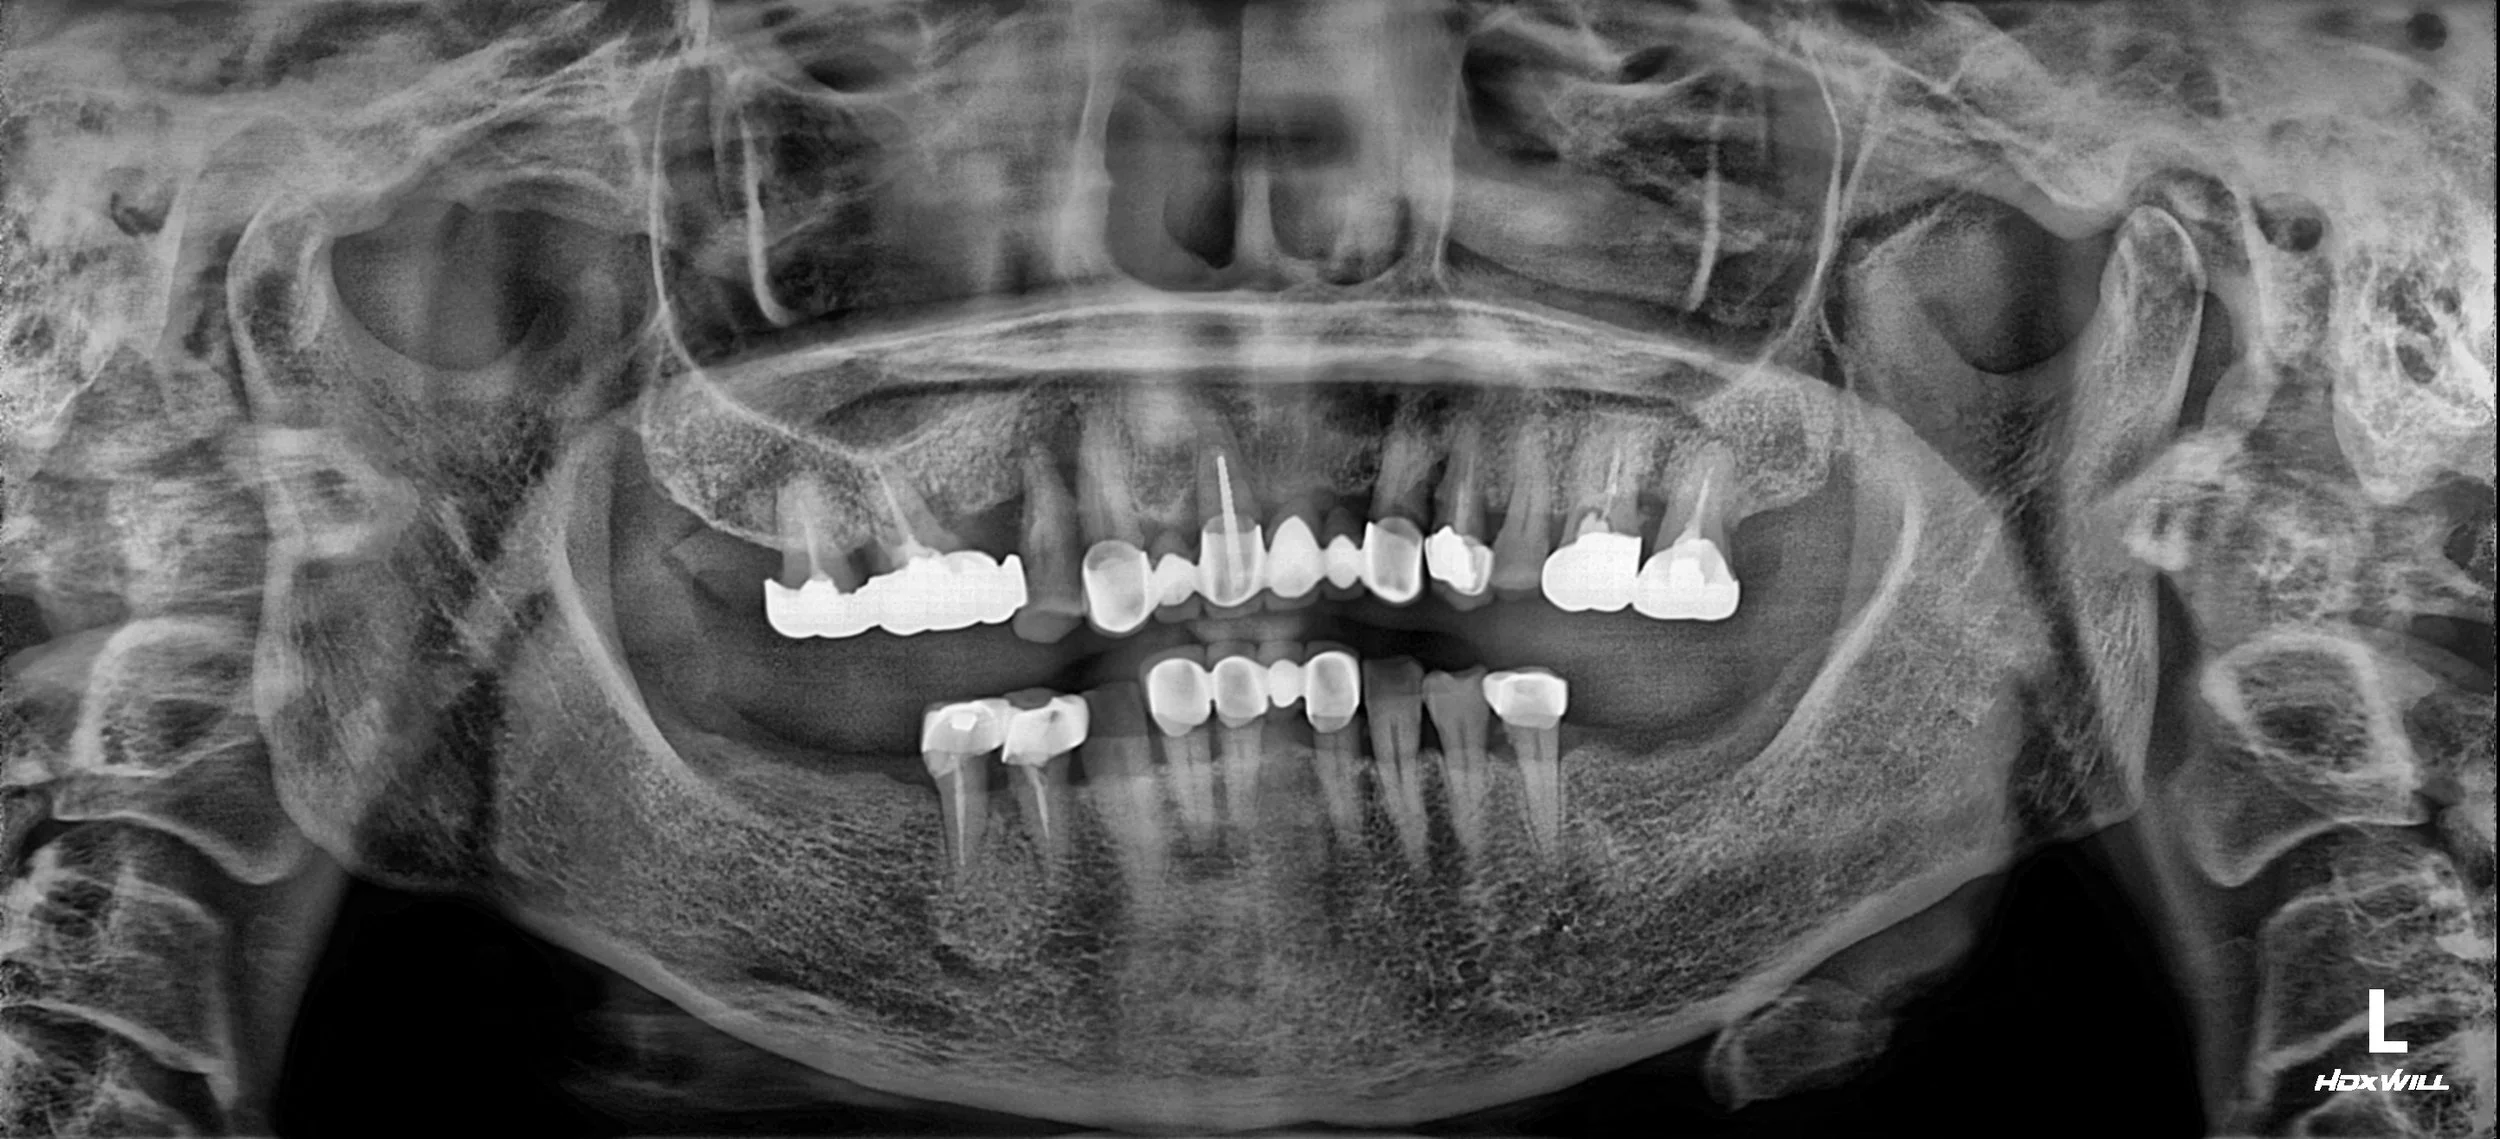

30. Strategic Full Mouth Rehabilitation: Balancing Clinical Goals and Financial Constraints

VDO Elevation and Aesthetic Reconstruction in a Male Patient in his 70s. A Cost-Effective Approach Restoring Functional Support up to the First Molars while Maximizing Natural Tooth Preservation.